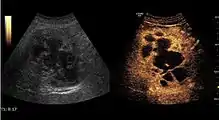

It is the most common liver tumor with a prevalence of 0.4 – 7.4%. It is generally asymptomatic but also can be associated with pain complaints or cytopenia and/or anemia when it is very bulky. It is unique or paucilocular. It can be associated with other types of benign liver tumors. Characteristic 2D ultrasound appearance is that of a very well defined lesion, with sizes of 2–3 cm or less, showing increased echogenity and, when located in contact with the diaphragm, a "mirror image" phenomenon can be seen. When palpating the liver with the transducer the hemangioma is compressible sending reverberations backwards. Doppler exploration reveals no circulatory signal due to very slow flow speed. CEUS investigation has real diagnosis value due to the typical behavior of progressive CA enhancement of the tumor from the periphery towards the center. The enhancement is slow, during several minutes, depending on the size of hemangioma and on the presence (or absence) of internal thrombosis. During late (sinusoidal) phase, if totally "filled" with CA, hemangioma appears isoechoic to the liver. Deviations from the above described behavior can occur in arterialized hemangiomas or those containing arterio-venous shunts. In these cases, differentiation from a malignant tumor is difficult and requires other imaging procedures, follow up and measurements of the tumor at short time intervals.[4]